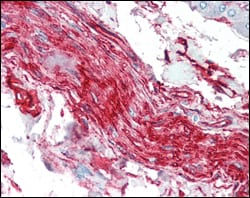

IHC 1/200 - 1/1000 Human,Mouse,Rat

Antibodies targeting S100A10/P11 are essential tools for studying its expression, localization, and function. They are widely used in techniques like Western blotting, immunohistochemistry, and immunofluorescence to investigate its overexpression in tumors (e.g., colorectal, breast cancers) or reduced levels in neurological conditions. These antibodies also aid in elucidating S100A10/P11’s role in tumor angiogenesis, cell adhesion, and synaptic plasticity. Their diagnostic and therapeutic potential is under exploration, particularly in targeting cancer metastasis pathways or modulating neurotransmitter systems. Validation of specificity remains crucial, as cross-reactivity with other S100 proteins can occur.